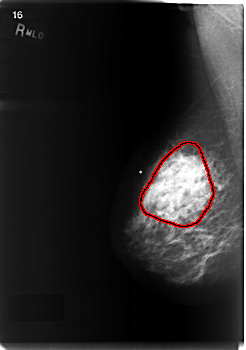

C_0471_1.RIGHT_MLO

RIGHT_MLO LINES 5936 PIXELS_PER_LINE 4168 BITS_PER_PIXEL 12 RESOLUTION 50 OVERLAY

FILE: C_0471_1.RIGHT_MLO.OVERLAY

TOTAL_ABNORMALITIES 1

ABNORMALITY 1

LESION_TYPE MASS SHAPE ASYMMETRIC_BREAST_TISSUE MARGINS ILL_DEFINED

ASSESSMENT 5

SUBTLETY 5

PATHOLOGY MALIGNANT

TOTAL_OUTLINES 1

BOUNDARY